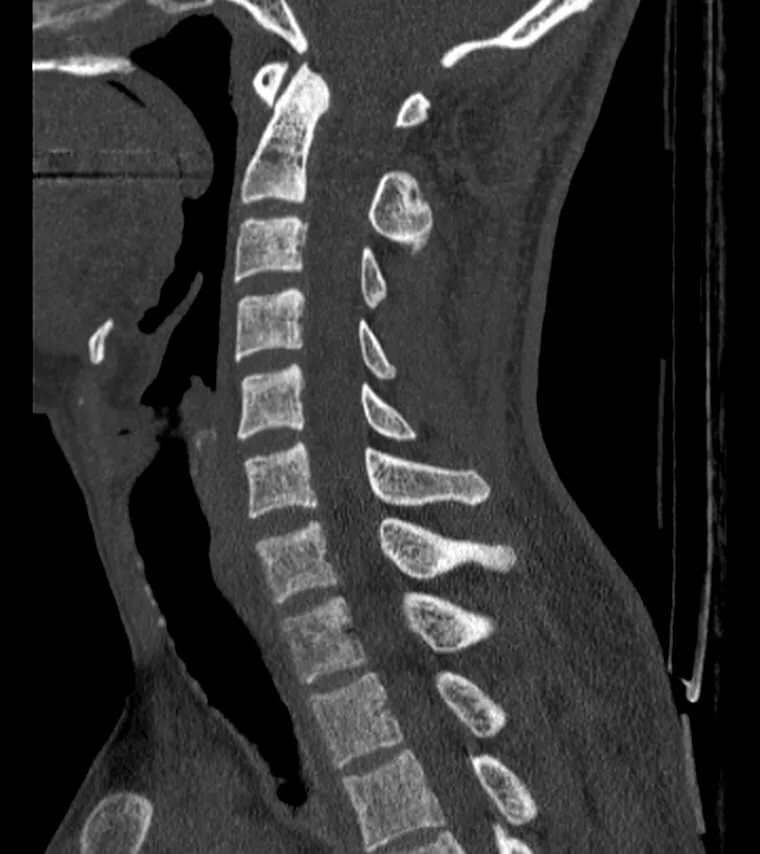

КТ позвоночника - это высокотехнологичное обследование, построенное на принципе послойного сканирования позвоночного столба с помощью рентгеновских лучей под различными ракурсами. По показателям информативности эта методика значительно превосходит обычный рентген - на МСКТ томограммах можно увидеть аномалии развития и патологические изменения размером до 1 мм. Записаться на мультиспиральную КТ позвоночника в Санкт-Петербурге можно разными способами, но легче всего найти подходящий диагностический центр через Интернет. В этом вам поможет наш сайт. Мы собрали в каталоге все клиники Санкт-Петербурга, делающие КТ обследование, с ценами и адресами, чтобы вы могли выбрать лучший вариант. Обращайтесь, мы будем рады помочь найти нужное диагностическое предложение для вас и ваших близких. Что покажет КТ позвоночного столба? Мультиспиральная КТ позвоночника делится на несколько отделов. Для сканирования выделяют: С помощью КТ поясничного отдела можно обнаружить причины болей в пояснице и онемен

С помощью КТ поясничного отдела можно обнаружить причины болей в пояснице и онемения нижних конечностей, особенно если совместить ее с КТ копчика. КТ шейного отдела хорошо визуализирует основание черепа и шейные позвонки. Ее часто проводят вместе с исследованием головного мозга. Это помогает получить дополнительную информацию о проблемах с его кровоснабжением. КТ грудного отдела поможет обнаружить причины боли в области ребер и сердца, затрудненного дыхания, причины лордоза, сколиоза, кифоза. Компьютерная томография позвоночника поможет обнаружить также опухоли костей и метастазы, трещины и переломы позвонков, стенозы спинномозгового канала, остеомиелит, артрозы, другие костные и хрящевые патологии.